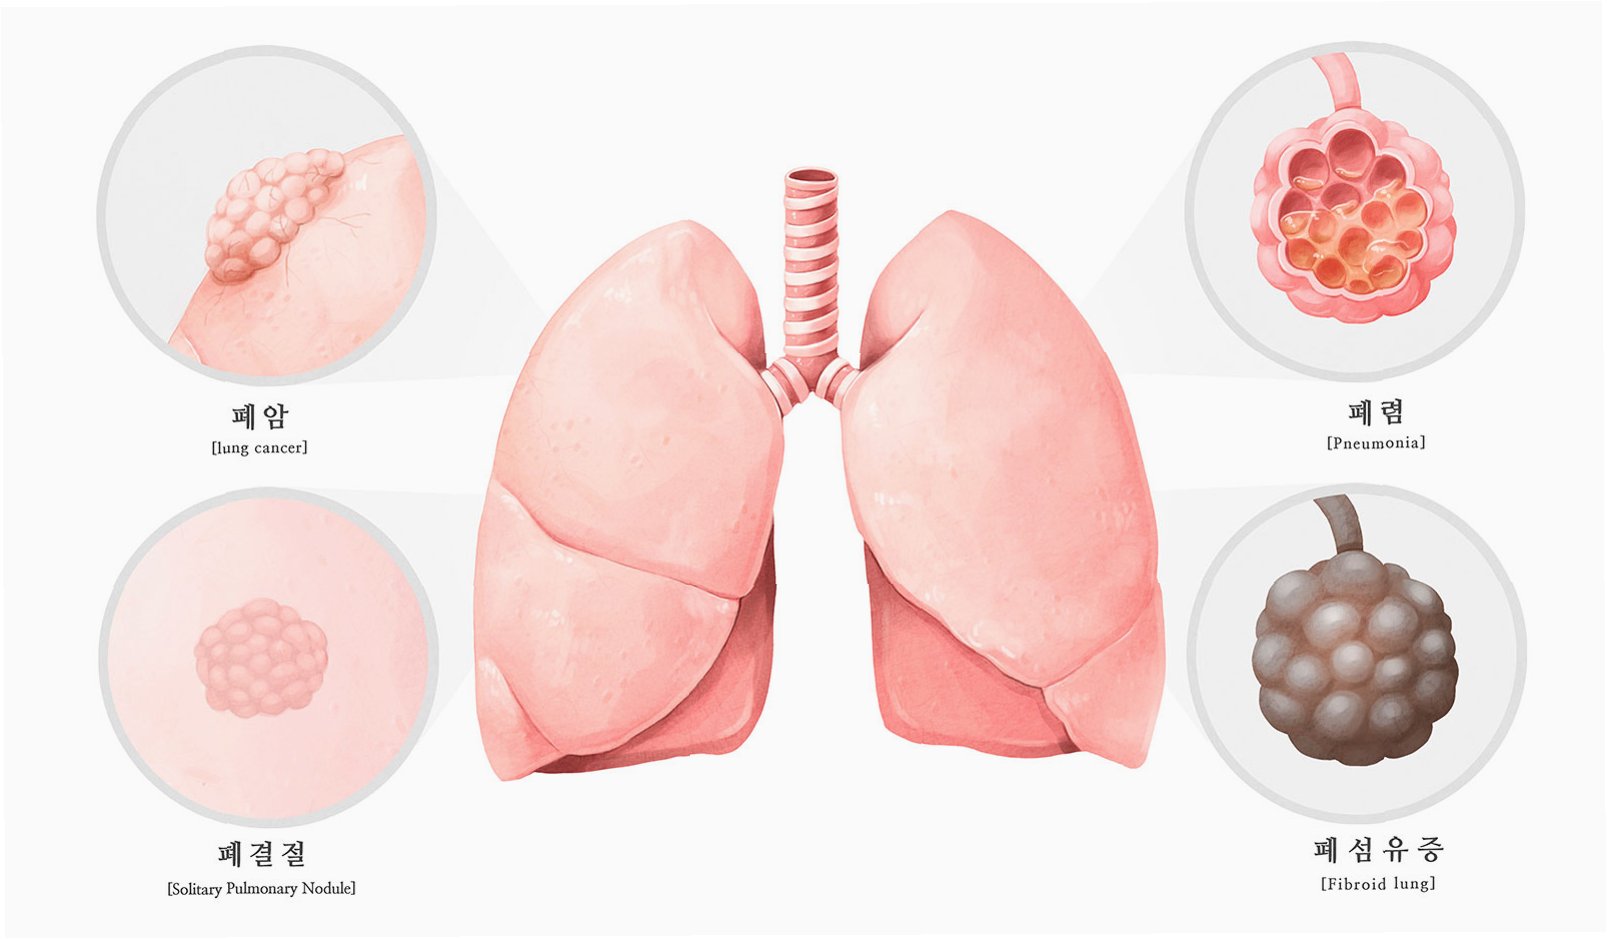

의료진은 이물질이 기관지에 박히면서 신체가 칼슘으로 둘러싸 격리하는 과정에서 석회화가 진행된 것으로 판단했습니다. 정밀 검사 결과, 좌측 폐는 5년간의 감염으로 기능을 완전히 상실한 상태였습니다. 의료진은 처음에는 석회화된 부분만 제거하려 했으나, 손상 범위가 너무 넓어 결국 폐 전체를 적출해야 한다는 결론에 이르렀습니다. 사이먼스 씨는 결국 왼쪽 폐를 떼어내는 수술을 받았습니다.

사이먼스 씨는 '작은 먼지 한 톨이 내 인생을 이렇게 바꿀 줄 몰랐다'며 '수술 동의서에 서명하던 순간이 인생에서 가장 무거웠다'고 심경을 토로했습니다. 전문가들은 외상으로 이물질이 체내에 남을 경우 장기간에 걸쳐 석회화가 진행되며 염증이나 조직 괴사를 일으킬 수 있다고 경고합니다. 특히 폐 조직은 통증 수용체가 적어 초기 증상 인지가 어렵고, 염증이 심해져야 발열, 기침, 호흡곤란 등이 나타날 수 있어 주의가 필요합니다.